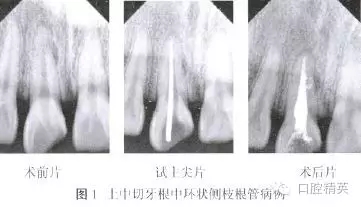

患者,男,24歲,因右上頜中切牙破損、變色10余年,近1個(gè)月反復(fù)出現(xiàn)牙齦腫脹、瘺管,咬合疼痛等癥狀。于2013年7月就診。檢查:右上中切牙牙冠色暗,切端近中斜折,髓腔暴露,內(nèi)有少量腐質(zhì),叩痛(+),無(wú)松動(dòng),頰側(cè)牙齦距離齦緣3 mm處可見(jiàn)瘺管。瘺管處牙齦腫脹約2 mm×2 mm。X線片示根管內(nèi)無(wú)充填物,根中近中側(cè)可見(jiàn)弧形低密度影像,根尖周圍低密度影像(圖1)。

紙尖干燥根管,2%葡萄糖酸洗必泰溶液浸泡根管1 min。紙尖干燥根管,使用螺旋充填器將氫氧化鈣糊劑導(dǎo)入根管內(nèi),氧化鋅嚴(yán)密封填?;颊?周后復(fù)診,牙齦瘺管及腫脹消失,患牙無(wú)叩痛,去除暫封物,3%次氯酸鈉溶液沖洗根管,去除氫氧化鈣。將牙膠尖35.~04使用GP Size Creator修剪至50.~04后試主尖,拍攝X線片示主尖尖端距離根尖約1 mm(圖1)。紙尖干燥根管,試熱壓尖F.一06、Buchanan垂直加壓器及23G熱牙膠回填膠囊針頭。紙尖干燥根管,3%次氯酸鈉溶液浸泡根管,I耐一Safe超聲蕩洗尖距工作長(zhǎng)度l mm連續(xù)蕩洗根管2次,每次20 s。

拍攝X線片根中遠(yuǎn)中側(cè)可見(jiàn)兩個(gè)側(cè)枝根管充填后形成的環(huán)形影像(圖1)。氧化鋅嚴(yán)密封填,擬觀察2周后行樁核冠修復(fù)。以上所有治療均得到患者知情同意。